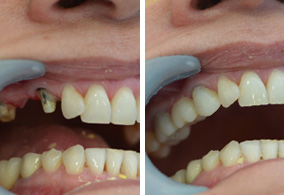

Sustituye los dientes que se han perdido con el paso de los años devolviendo funcionalidad y estética a tu boca.Un implante dental es un cilindro con forma de raíz dental fabricado de Material aloplástico (generalmente titanio) que se implanta quirúrgicamente debajo de las encías dentro del hueso maxilar o mandibular; una vez colocados y osteointegrado, el odontólogo colocara sobre ellos las coronas o puentes fijos que sustituirán a las piezas dentales perdidas, entonces el implante nos sirve para proveer retención y soporte a una prótesis dental fija o removible.

Con los Implantes Dentales no es necesario desgastar los dientes adyacentes para que sostengan a los dientes de reemplazo, no producen irritaciones ni nauseas, ni tienen que sujetarse a los dientes de ambos lados del espacio vacío como suele ocurrir con las prótesis o puentes comunes, podrás usar hilo dental brindando mayor limpieza, seguir conservando nivel de hueso, entre muchas otras ventajas.